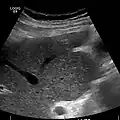

Ultrasound is routinely used in the evaluation of cirrhosis. It may show a small and nodular liver in advanced cirrhosis along with increased echogenicity with irregular appearing areas. Other liver findings suggestive of cirrhosis in imaging are an enlarged caudate lobe, widening of the fissures and enlargement of the spleen. An enlarged spleen (splenomegaly), which normally measures less than 11–12 cm in adults, can be seen and may suggest underlying portal hypertension. Ultrasound may also screen for hepatocellular carcinoma, portal hypertension, and Budd-Chiari syndrome (by assessing flow in the hepatic vein). An increased portal vein pulsatility is an indicator of cirrhosis, but may also be caused by an increased right atrial pressure.[34] Portal vein pulsatility can be quantified by pulsatility indices (PI), where an index above a certain cutoff indicates pathology:

Liver cirrhosis with ascites -

Liver cirrhosis as seen on a CT of the abdomen in transverse orientation

caudate lobe hypertrophy in ultrasound due to cirrhosis -

Hepatofugal flow in portal vein in ultrasound